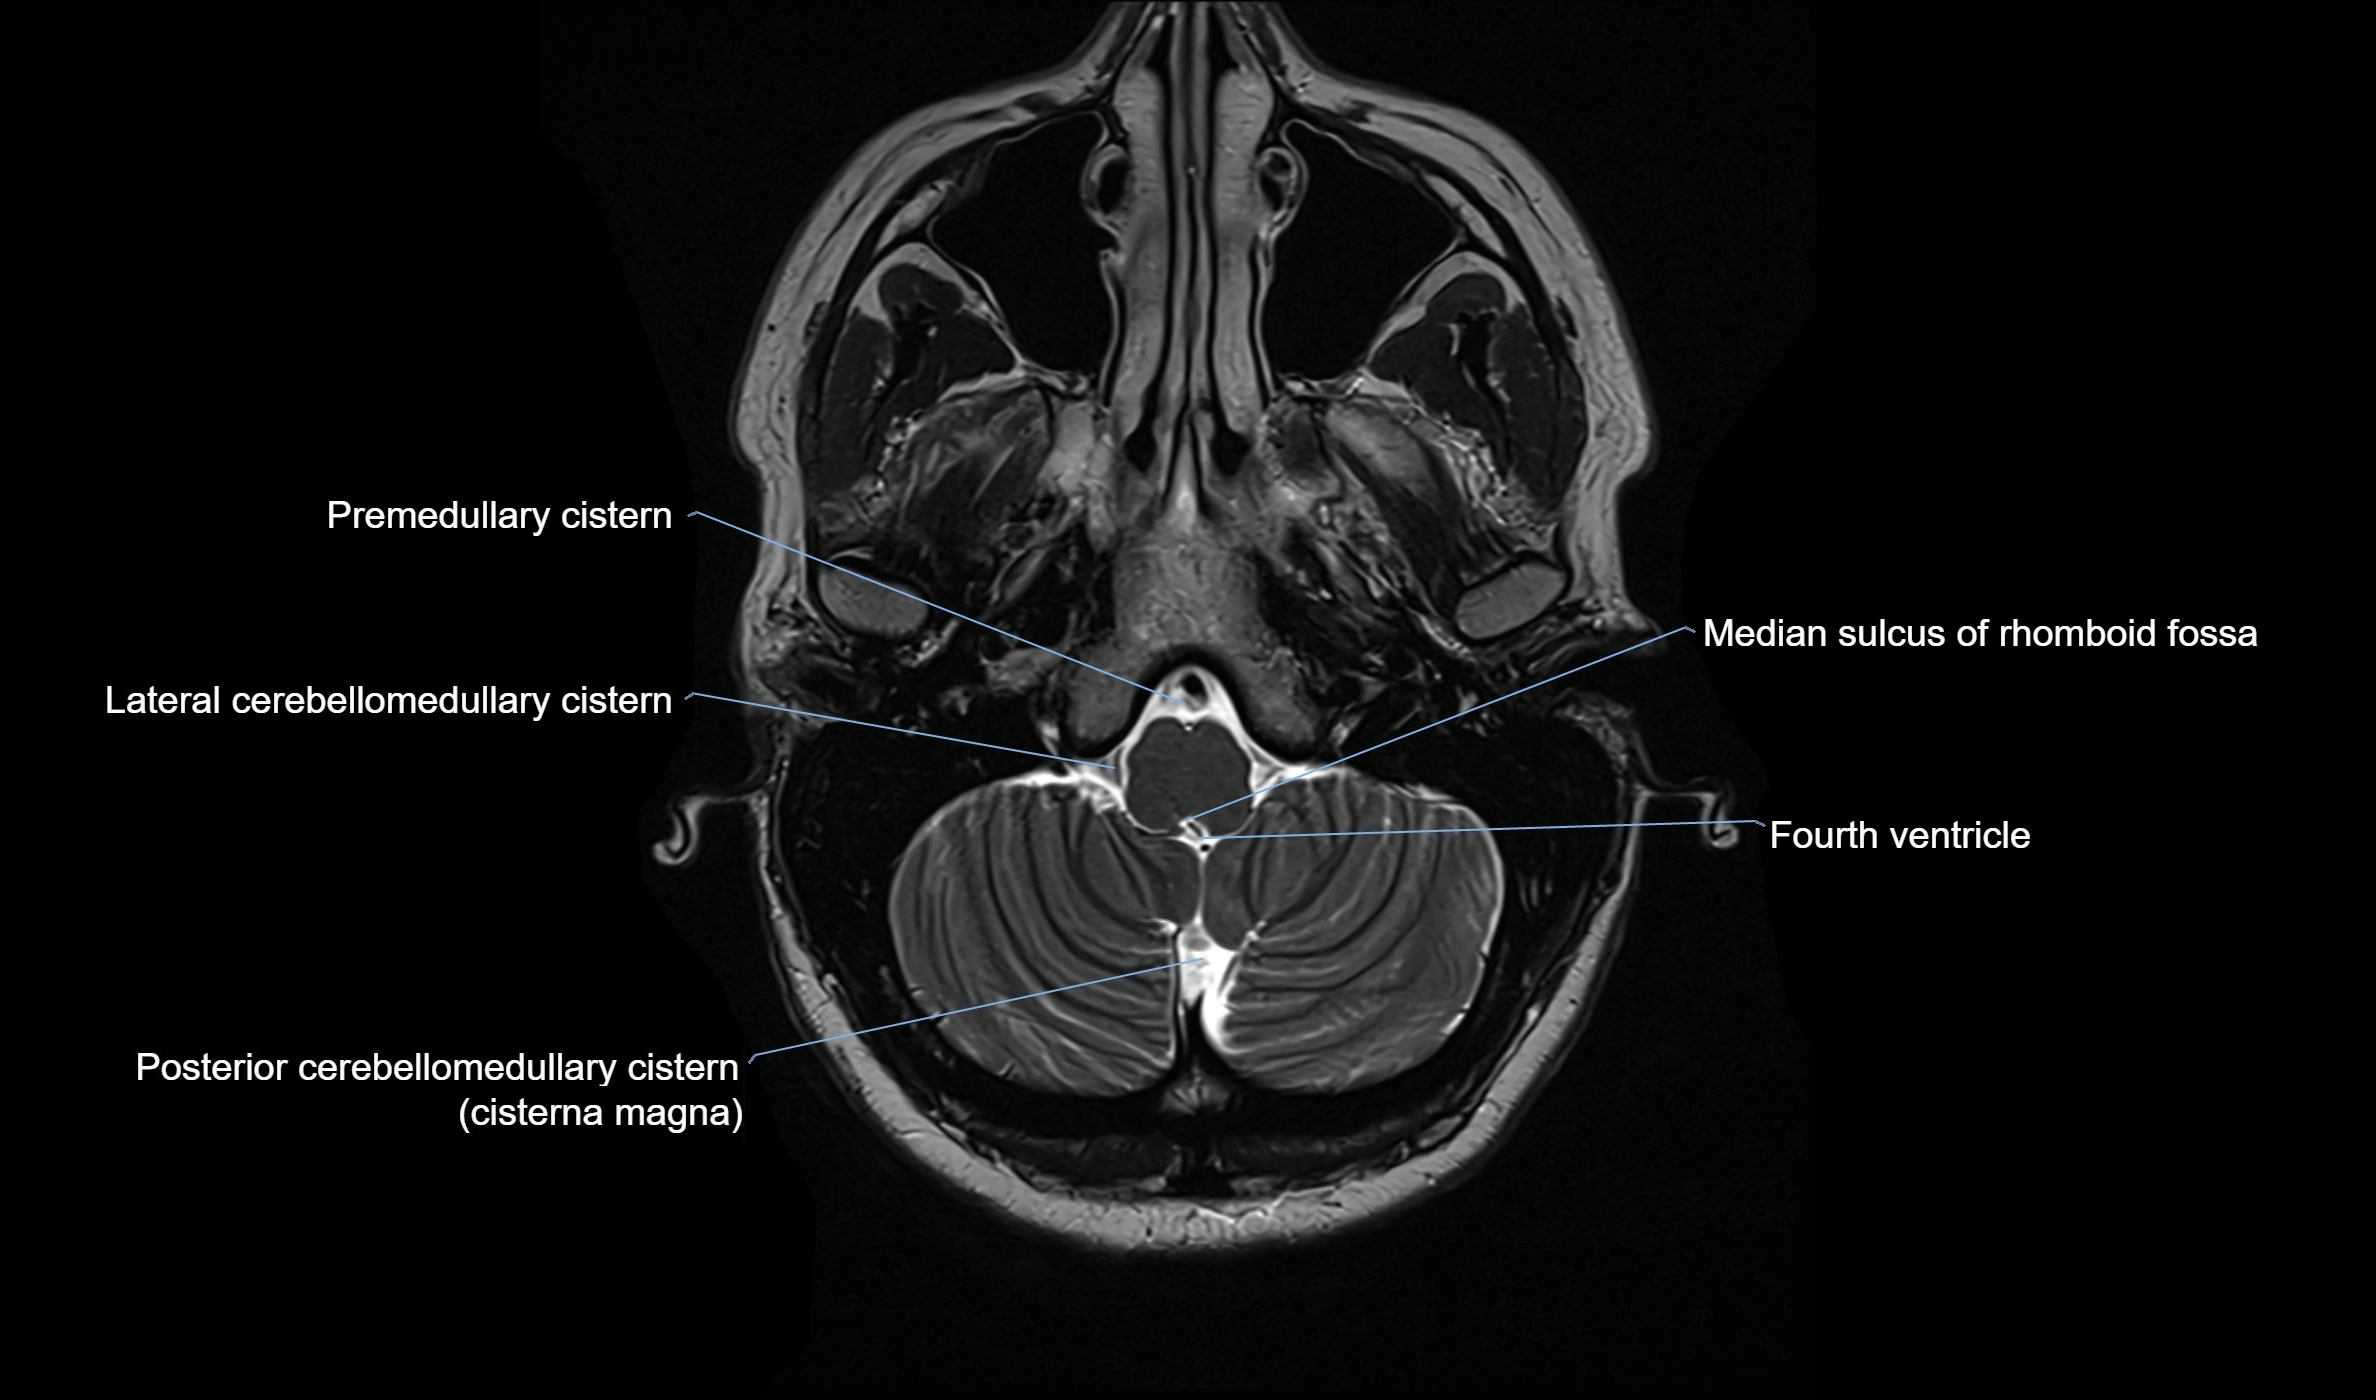

CT image

image